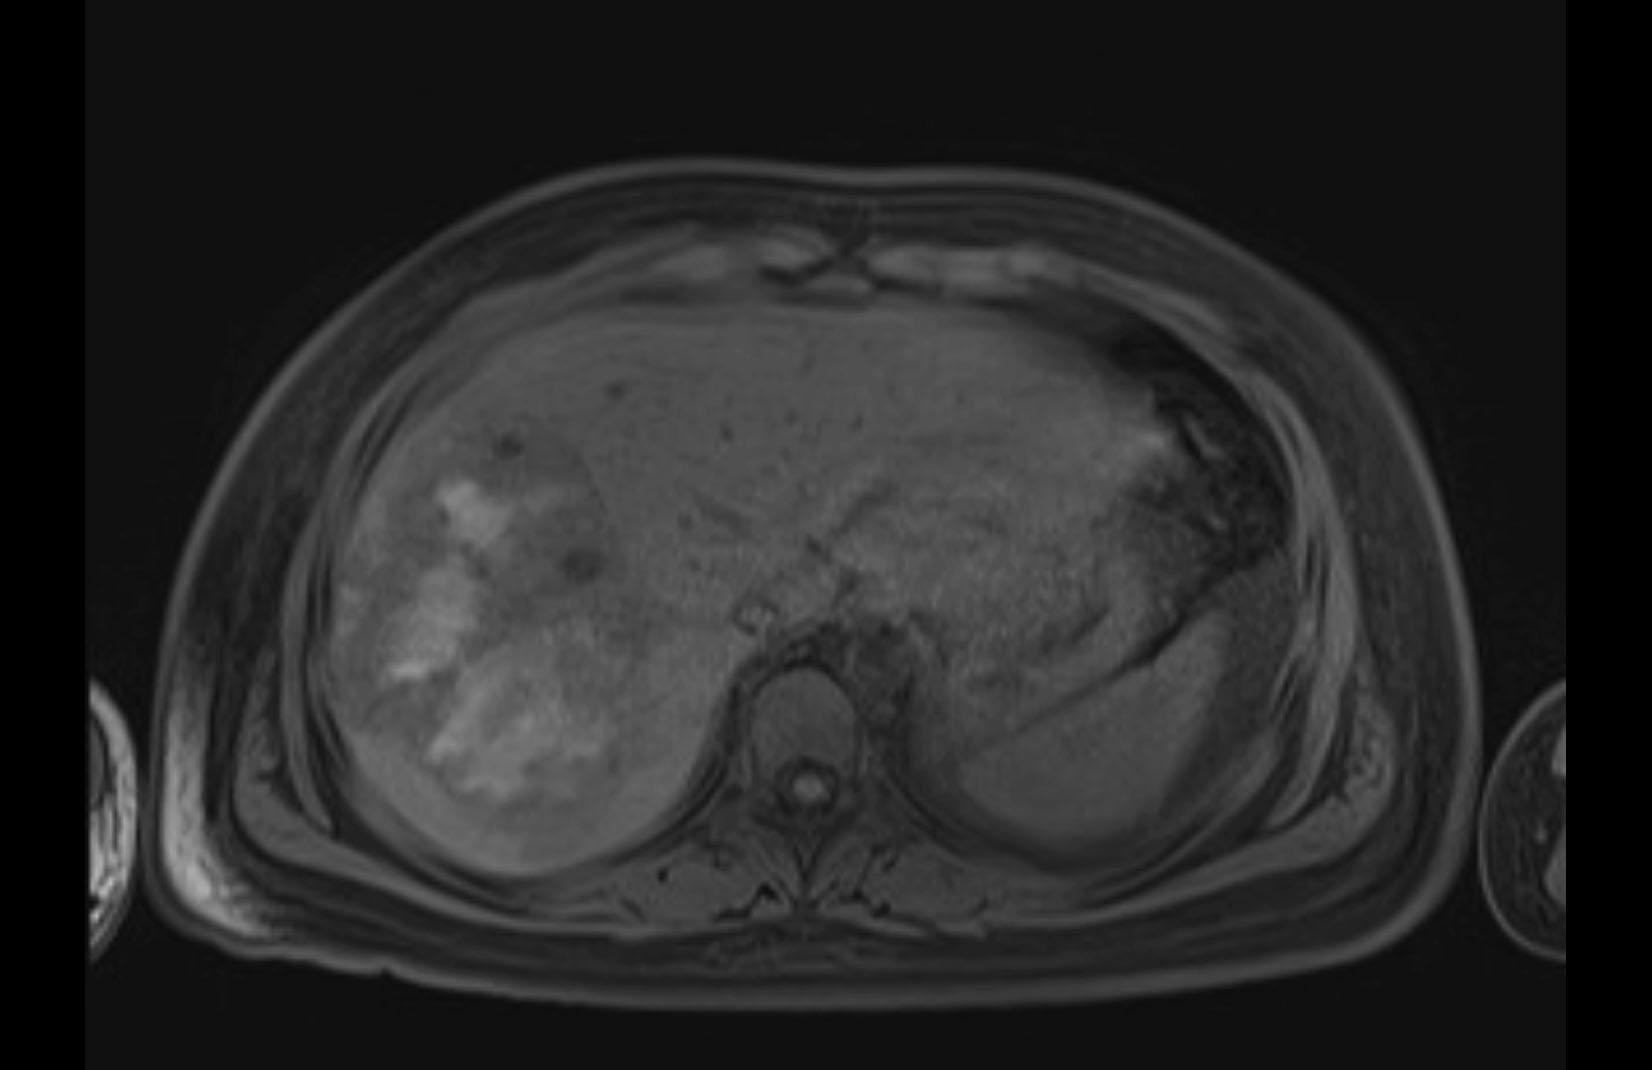

MRI T1